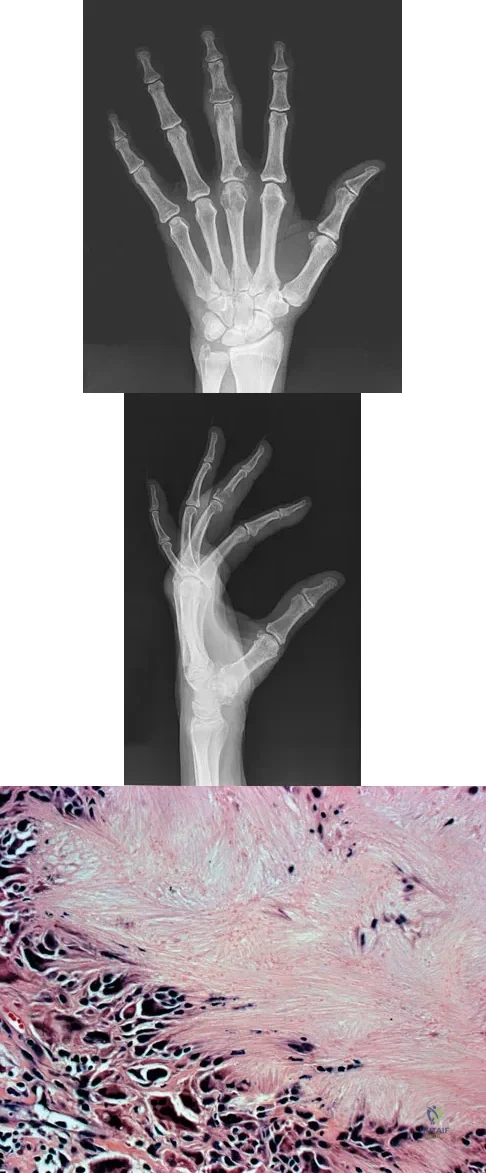

An 83-year-old woman reports pain in her left middle finger after a minor injury. Laboratory studies show a WBC count of 7,000/mm3, an erythrocyte sedimentation rate of 3 mm/h, a uric acid of 10.4 mg/dL, and a normal serum protein electrophoresis. Radiographs are shown in Figures 49a and 49b. A core biopsy specimen is shown is Figure 49c. In addition to treatment of the finger fracture, treatment should include

Explanation